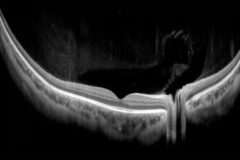

The cataract mode in the REVO series opens up new possibilities for patients with challening cases.

This featureprovides visualisation of structures hidden beneath opaque layers, making it ideal for diagnosing eye conditions thatwere previously difficult or impossible to study in patients with cataract, corneal oedemas or very dense floaters.The cataract mode allows the scanning speed and sensitivity of the OCT to be modified for better visualisation ofpatients with opaque media.